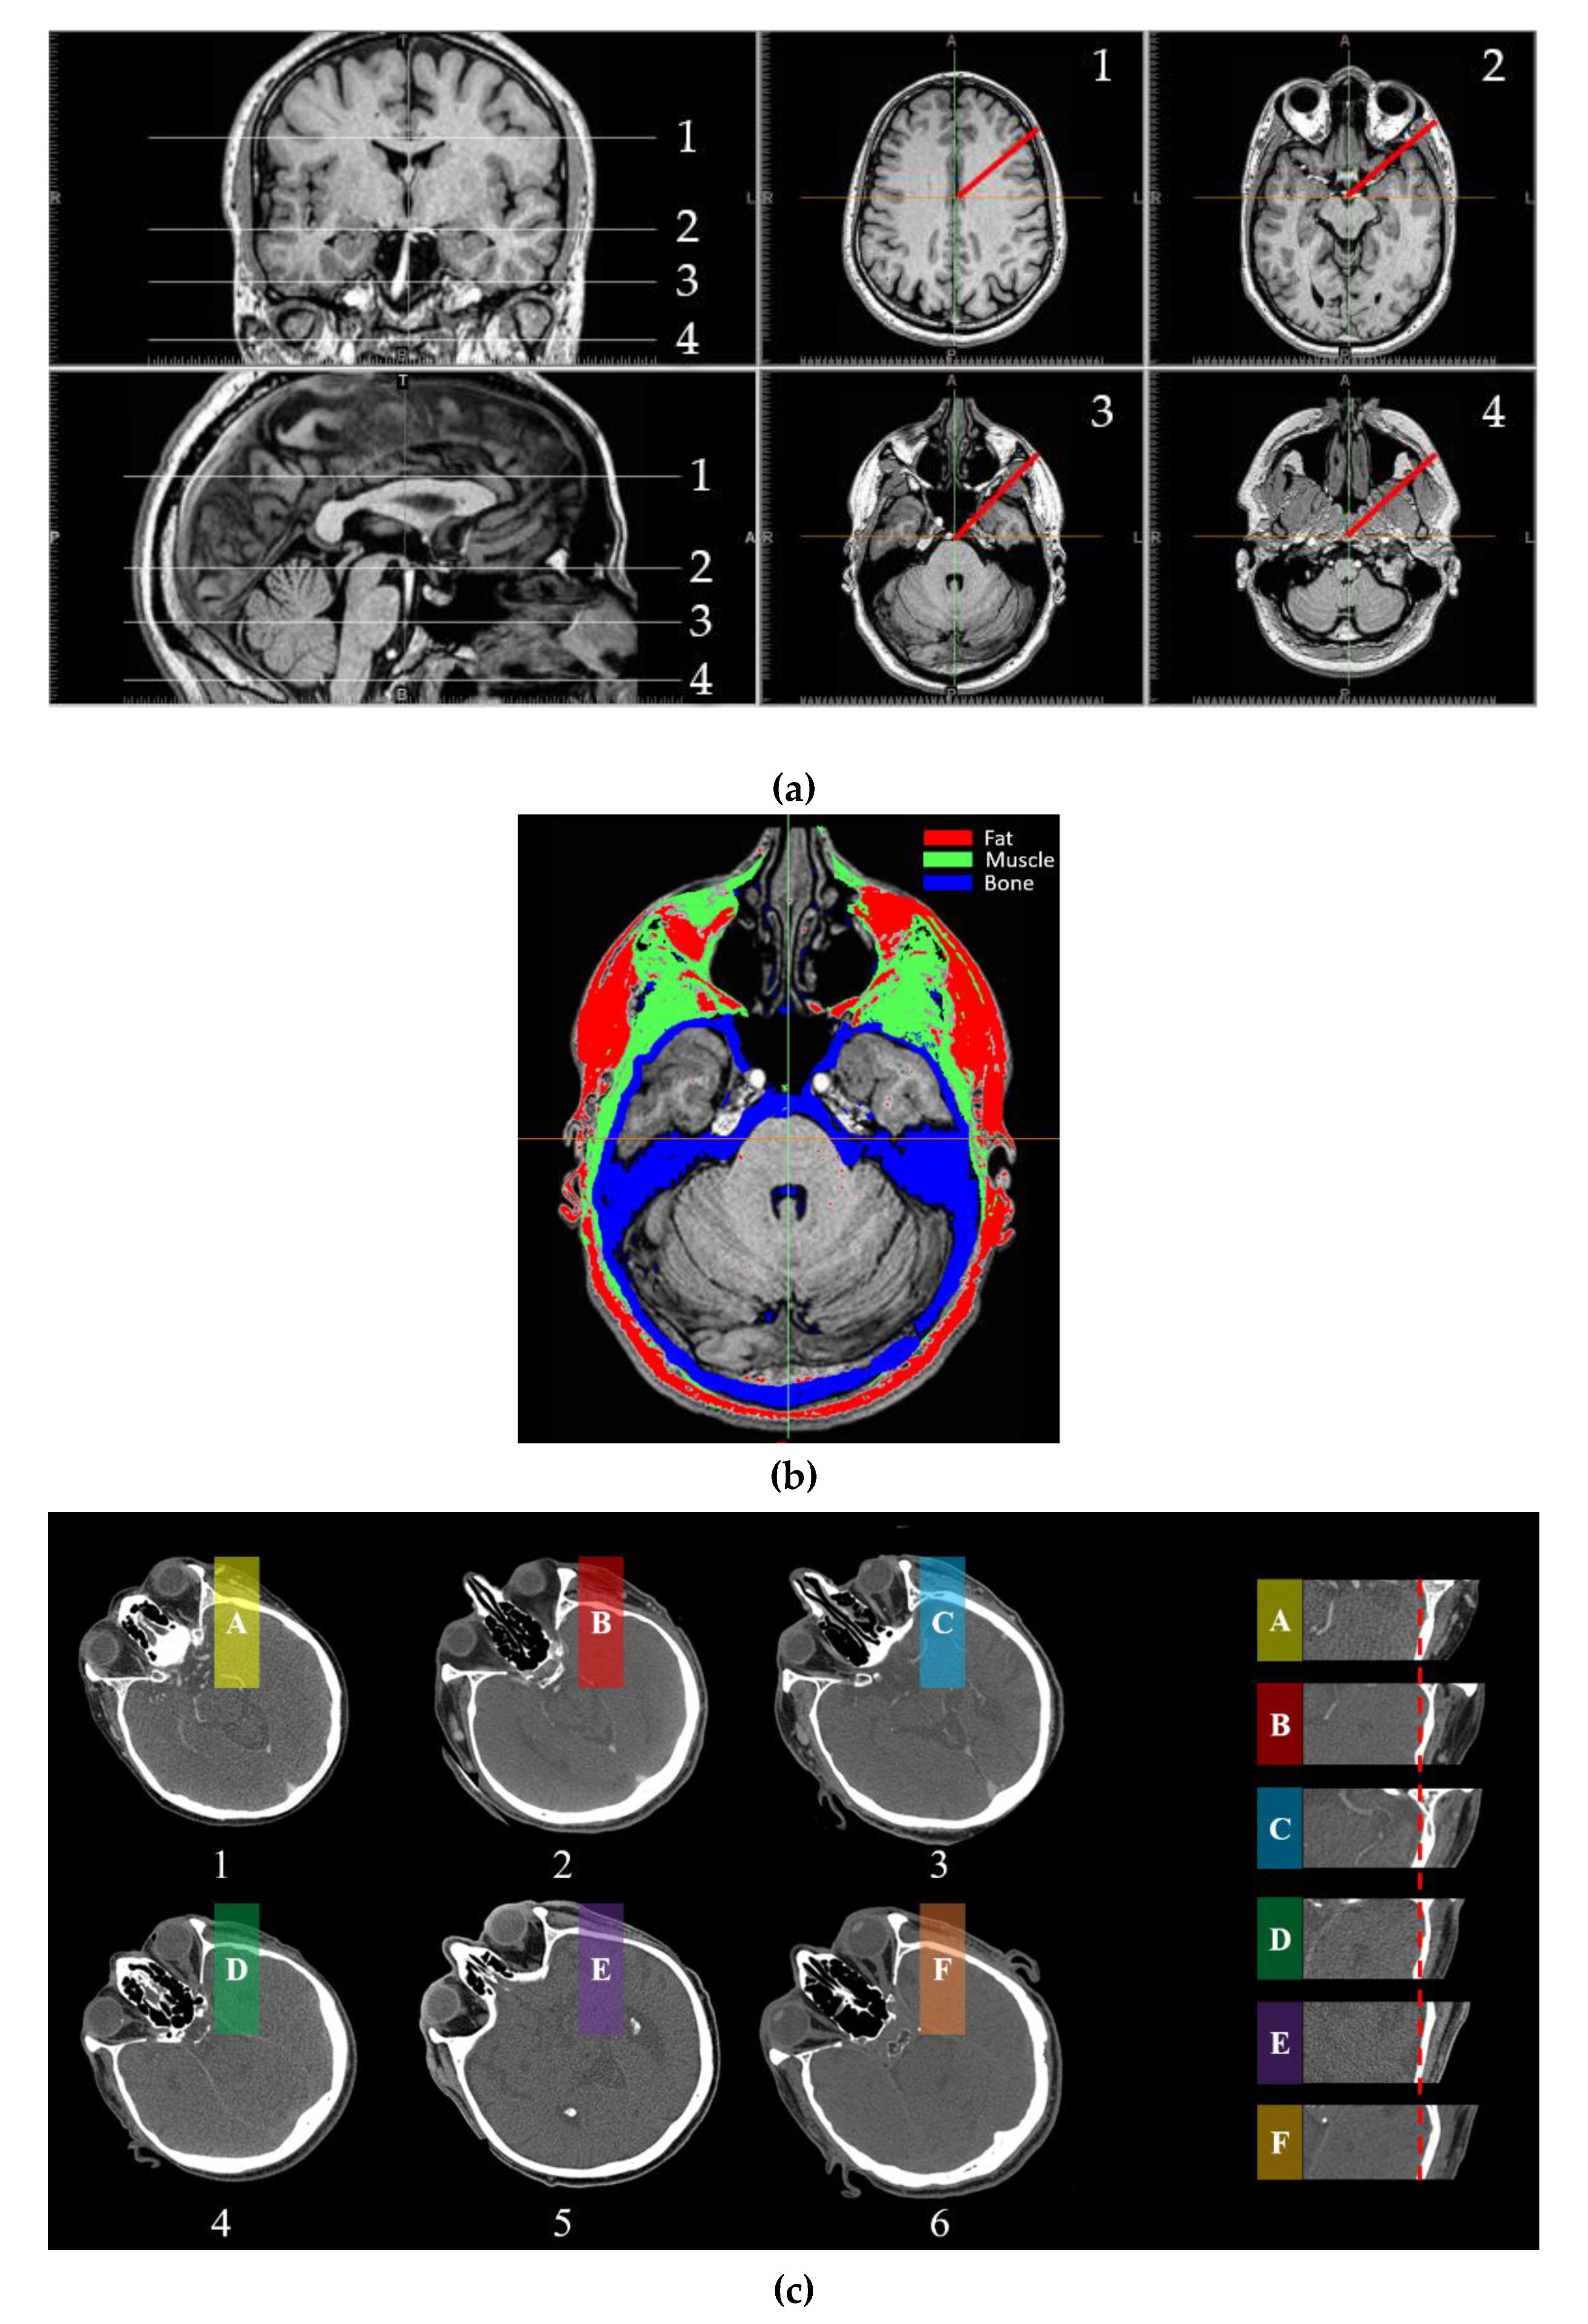

2.2. MRI Analysis of Head Composition and Structure

| 1 | 2 | 3 | 4 | ||||

|---|---|---|---|---|---|---|---|

| Tissue | Thickness (cm) | Tissue | Thickness (cm) | Tissue | Thickness (cm) | Tissue | Thickness (cm) |

| Brain | 8.81 | Brain | 7.37 | Brain | 1.37 | Muscle | 3.18 |

| Bone | 0.46 | Bone | 0.57 | Bone | 1.46 | Bone | 0.48 |

| Muscle | 0.31 | Muscle | 1.71 | Brain | 4.5 | Muscle | 3.56 |

| Fat | 0.78 | Fat | 0.75 | Bone | 0.66 | Bone | 0.58 |

| Skin | 0.27 | Skin | 0.31 | Muscle | 0.69 | Muscle | 0.46 |

| - | - | - | - | Fat | 0.76 | Fat | 0.52 |

| - | - | - | - | Skin | 0.36 | Skin | 0.4 |